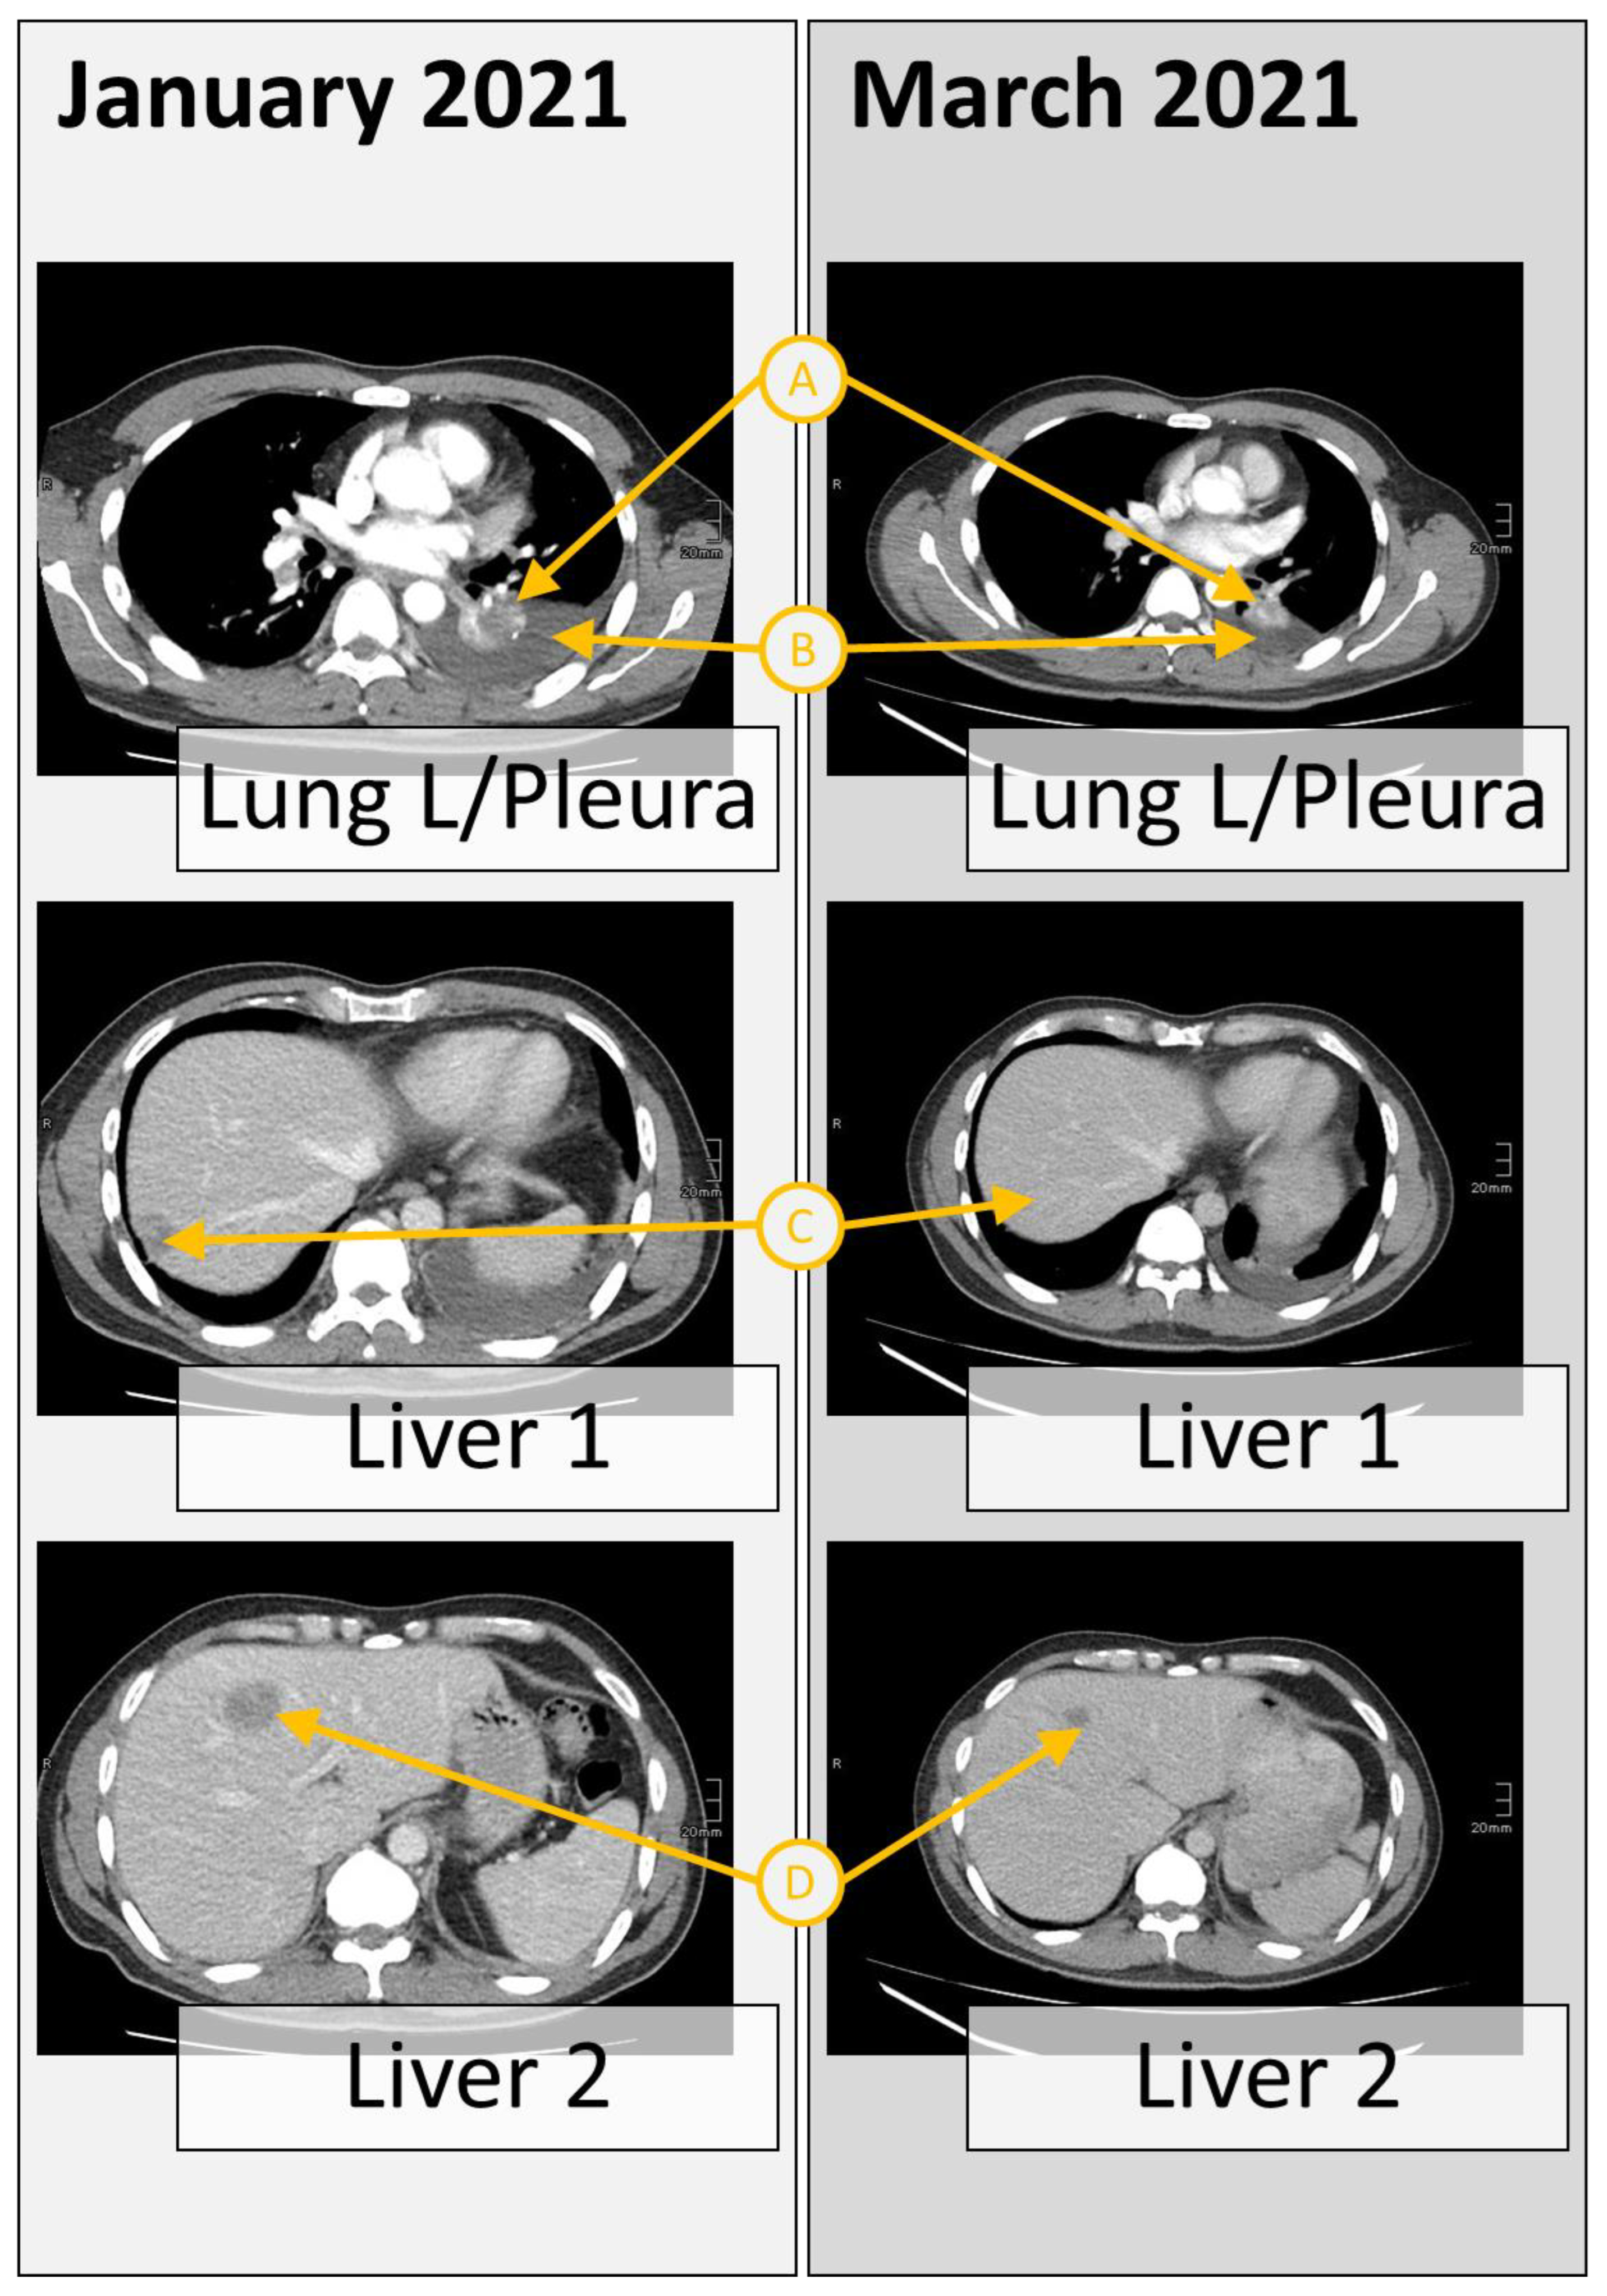

2. Case Presentation